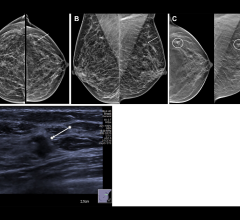

The LOGIQ e is the newest member of GE’s Compact Series of ultrasound systems. The system is designed with the speed, image quality and applications to support real-time clinical decisions in emergency settings.

It allows clinicians to view small anatomy clearly, and the system has advanced connectivity features that streamline clinical workflow by allowing clinicians to take the ultrasound exam to the patient at remote locations. With the system’s on-board image storage, it is seemingly a noteworthy imaging solution for the emergency department.